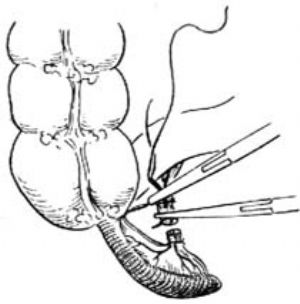

3.當闌尾位於盲腸後,位置固定不易切除時,可切開盲腸外下方的後腹膜[圖3 ⑴],再用紗布包住盲腸向上翻轉,露出闌尾後,作逆行闌尾切除術。另若闌尾較長伴管端粘連固定,不宜按常規勉強提出末端,改爲逆行切除闌尾。先用變止血鉗在靠近闌尾根部處穿過其系膜,帶過兩根4-0號絲線,雙重結紮闌尾根部[圖3 ⑵]。在結紮遠端1cm處夾一把彎止血鉗,用刀在止血鉗與結紮線之間切斷。闌尾殘端消毒處理後,根據具體情況行荷包縫合包埋或褥式縫合包埋。再用彎止血鉗向闌尾尖端方向分段鉗夾、切斷闌尾系膜[圖3 ⑶]最後切除闌尾,一一結紮近端闌尾系膜。

⑶分段鉗夾、切斷闌尾系膜